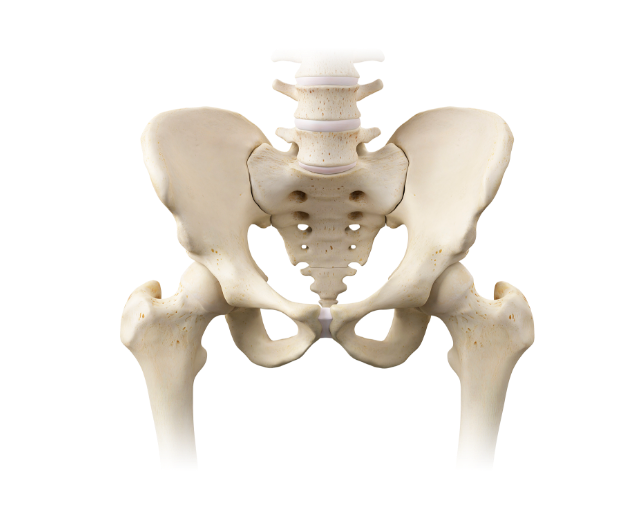

Total hip replacement고관절

고관절은, 공처럼 생긴 대퇴골두(femoral head)와 이를 감싸고 있는 소켓 모양의 골반골의 비구(acetabulum)로이루어져 있습니다. 고관절은 주로 체중 부하와 체중 전달의 기능을 하는 볼-소케트형의 활막 관절입니다.

고관절 중 양쪽, 즉 대퇴골두와 비구를 인공관절로 교체하는 수술입니다.